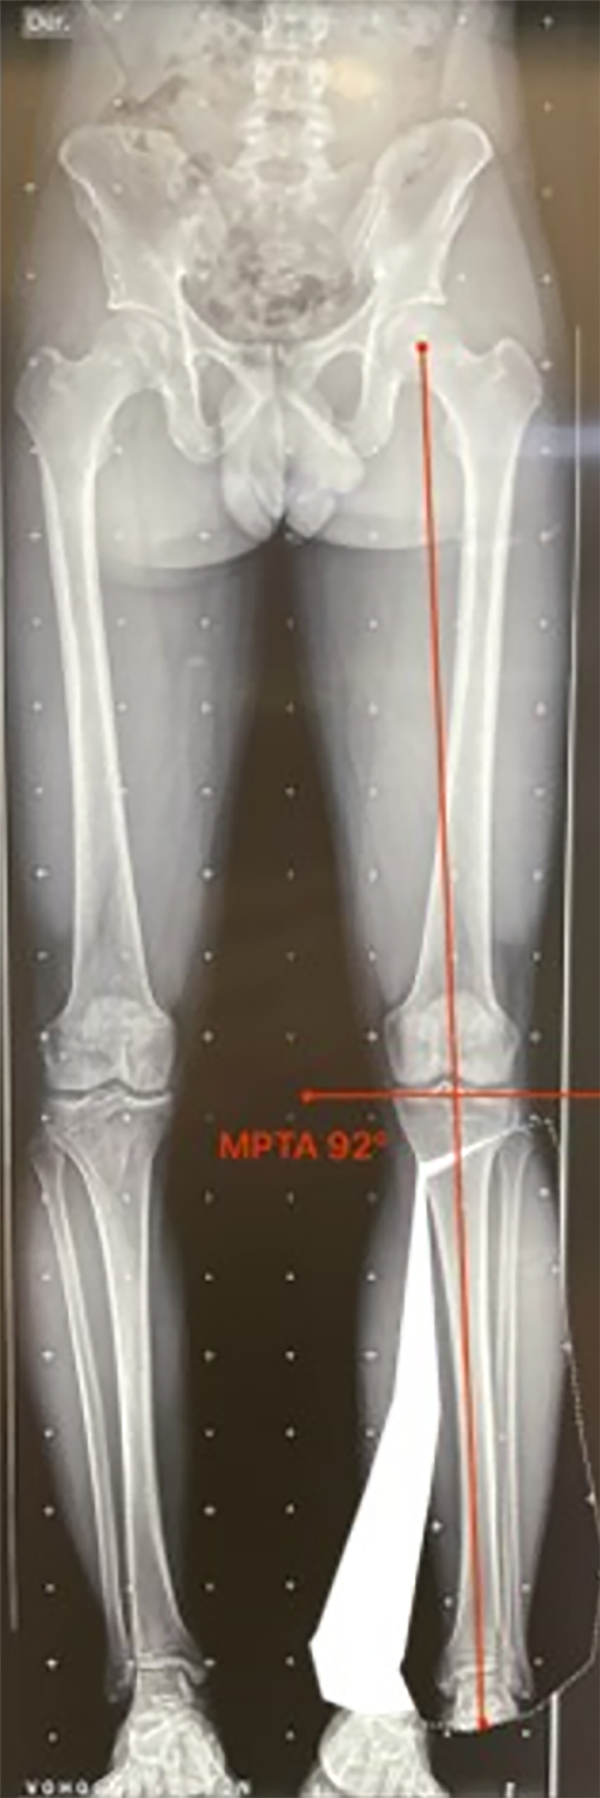

Figura 4: Ángulo femoral distal lateral mecánico (mLFDA): mLDFA y MPTA bilateral, se observa del lado izquierdo una deformidad en varo del fémur 92° (normal 85-90°) y la tibia 84° (normal 85-90°). Lado derecho con una deformidad en varo del fémur 92° y la tibia 87° en valor normal.